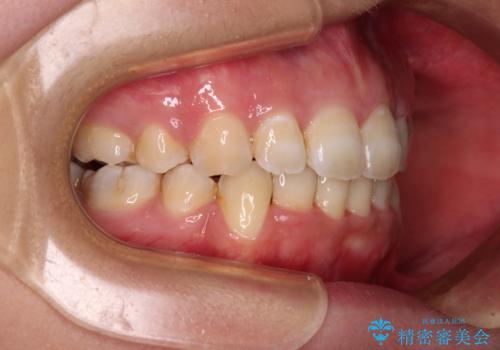

4本の歯を抜歯したことで、飛び出していた口元が引っ込み、横顔が大きく改善されました。

咬み合わせが悪化することのないようにスペースを閉じていくことができ、比較的スムーズに治療を進めることができました。